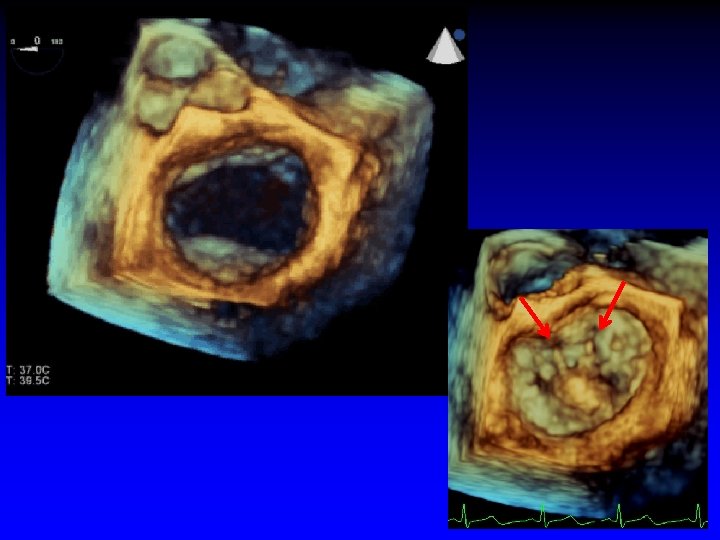

6. Grasping of the Leaflets PML AML

7. Post-Clip Placement Assessment Echo Guidance • Degeree of MR • Diastolic transmitral gradient • Achievement of double orifice Then, close the clip incrementally under echo-guidance